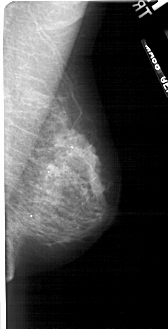

A_1723_1.LEFT_MLO

LEFT_MLO LINES 5461 PIXELS_PER_LINE 2356 BITS_PER_PIXEL 12 RESOLUTION 43.5 OVERLAY

FILE: A_1723_1.LEFT_MLO.OVERLAY

TOTAL_ABNORMALITIES 1

ABNORMALITY 1

LESION_TYPE CALCIFICATION TYPE PLEOMORPHIC DISTRIBUTION SEGMENTAL

ASSESSMENT 4

SUBTLETY 3

PATHOLOGY MALIGNANT

TOTAL_OUTLINES 1

BOUNDARY